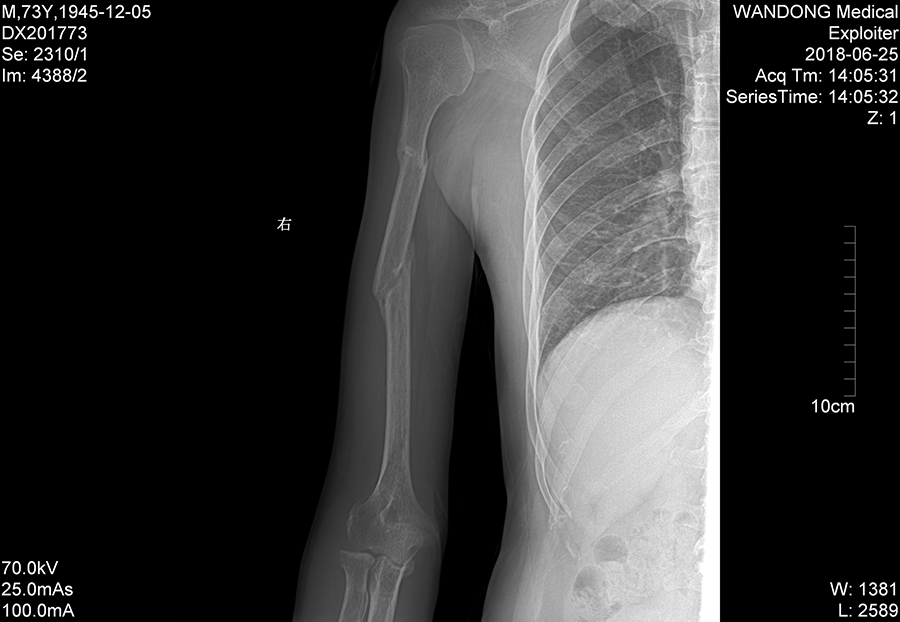

经过半个月小心治疗后,李大伯的手臂肿胀消退,伤情稳定下来,而后继续绑固治疗并辅助相关药物。8周后再次拍片,伤肢已经没有疼痛感,经拍片显示有较多骨痂形成,可以拆除夹板了。又再次小心嘱咐李大伯,要逐渐加强伤肢的功能训练,避免过早用力,估计半年左右就能痊愈了。